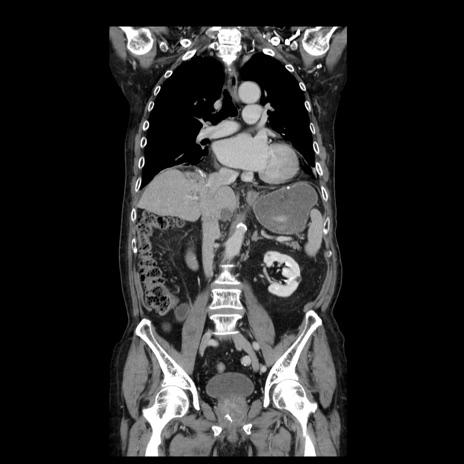

症例21(冠状断像)

【症例】70歳代男性

【主訴】腹痛

【現病歴】肝硬変・肝細胞癌にてかかりつけの方。約9時間前に食後より腹痛出現。症状が徐々に増悪し、嘔吐出現したため来院。

【既往歴】肝硬変、肝細胞癌(RFA、TACE後)

【身体所見】意識清明、表情苦悶様、BT 36℃、BP 129/78mmHg、P 88bpm、SpO2 97%(RA)、右上腹部から心窩部にかけて圧痛あり、反跳痛なし、筋性防御あり。

【データ】WBC 5800、CRP 0.16